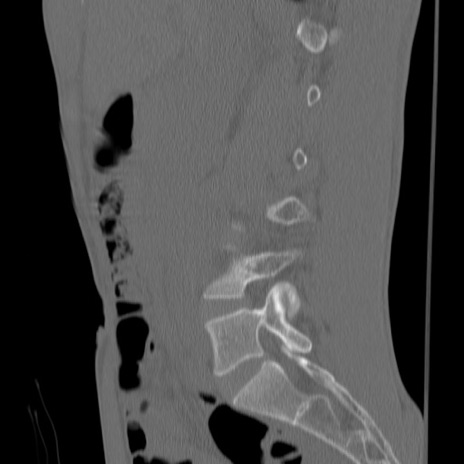

症例3 腰椎CT(矢状断像)

【症例】30歳代男性

【主訴】腰痛

【現病歴】本日旅行先で観光中に、友人と衝突し転倒し受傷。

【身体所見】麻痺なし、右下腿内側前面外側、左下腿内側に知覚鈍麻・しびれ

異常所見と診断は?

腰椎CT